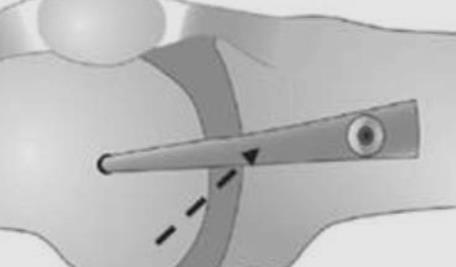

Medial Collateral Ligament or MCL is a band of tissues on the inner aspect of the knee. It runs from the thighbone to about six cms below the knee joint to the shinbone. Sportsmen playing soccer, hockey, and basketball or skiing are more likely to suffer from Medial Collateral Ligament (MCL) Tear. Also MCL tear can result from motor vehicle accidents. MCL is the most important stabilizer of the knee, crucial for normal knee function.

MRI scan helps to know the extent of the MCL tear, and the condition of the other ligament structures. It is not uncommon to see associated meniscal injuries in cases of MCL tear.